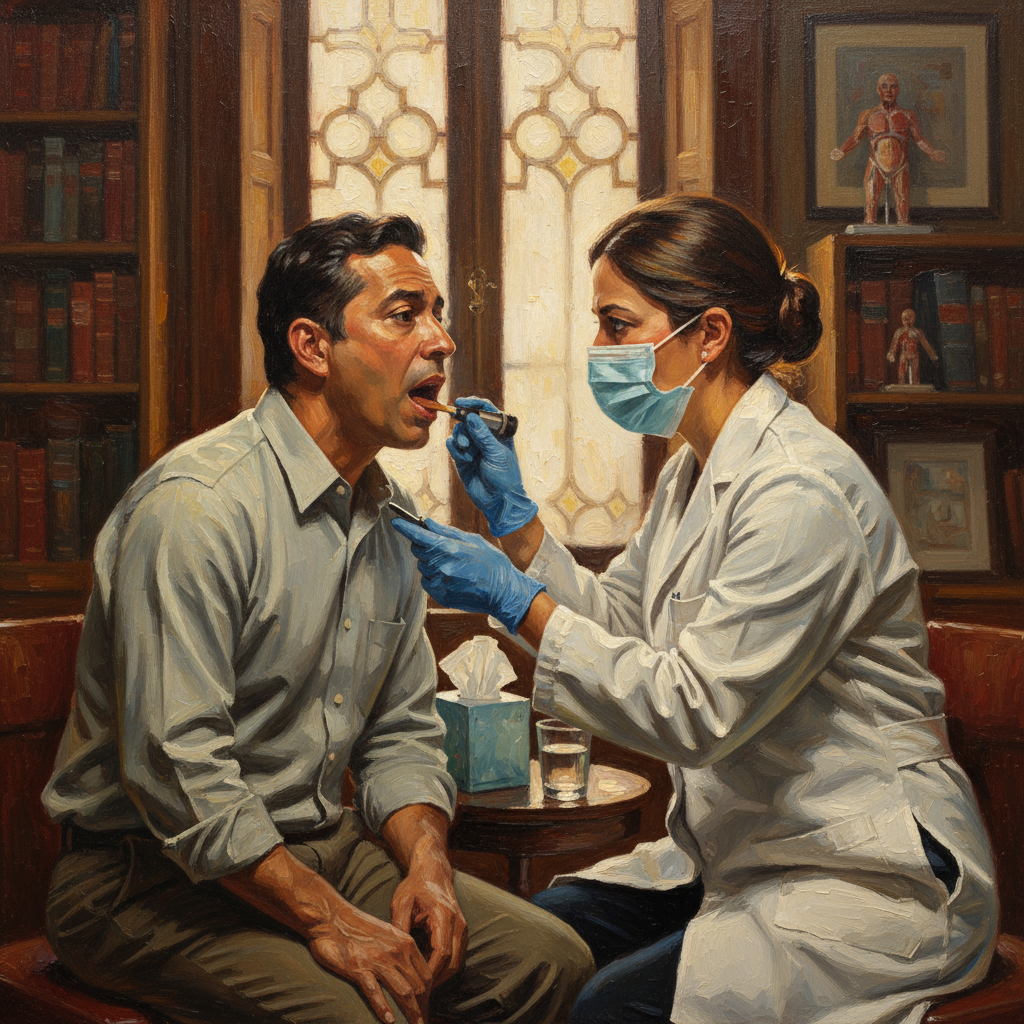

Qué Esperar en la Consulta Médica

Tu médico probablemente realizará:

- Historia clínica detallada: Duración, características de las flemas, síntomas asociados

- Examen físico: Auscultación pulmonar, examen de garganta y nariz

- Posibles estudios: Radiografía de tórax, cultivo de esputo, exámenes de sangre si se sospecha infección bacteriana

Preguntas que debes hacer a tu médico:

- “¿Es necesario un antibiótico o esto se resolverá naturalmente?”

- “¿Qué puedo hacer en casa para acelerar la recuperación?”

- “¿Cuándo debo regresar si los síntomas no mejoran?”

- “¿Hay algo en mi estilo de vida que pueda estar contribuyendo?”